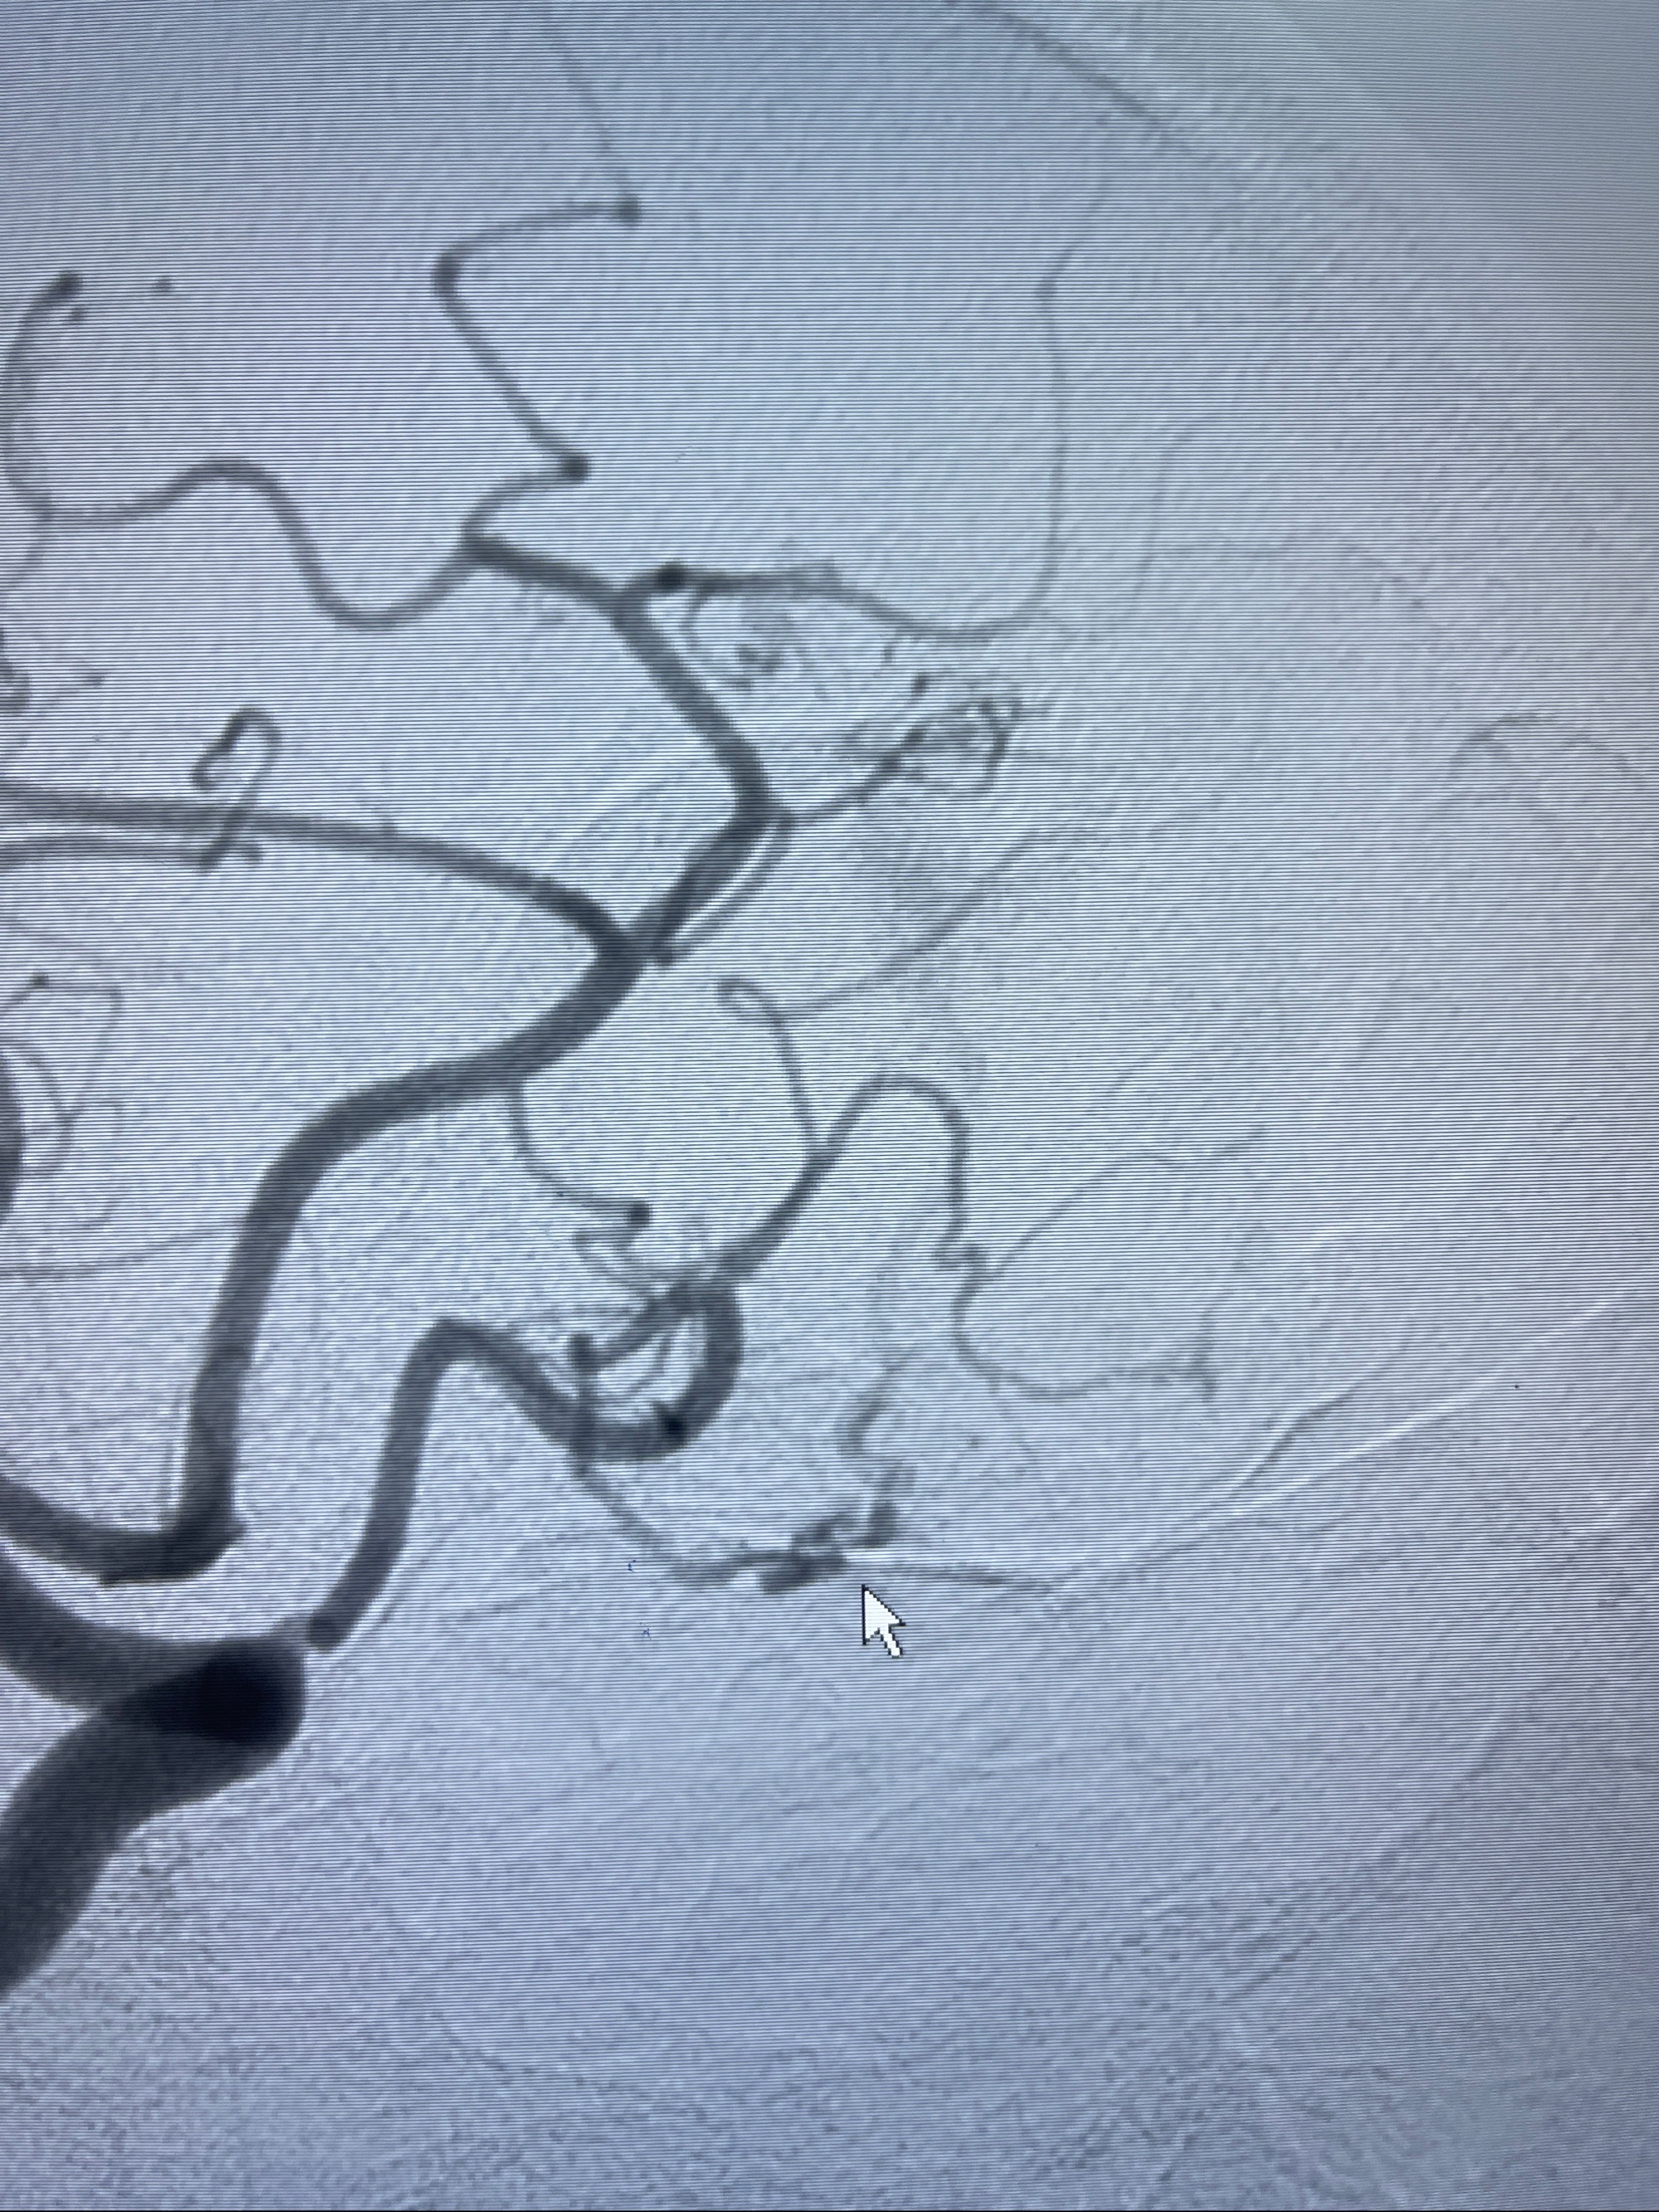

2023-09-13全脑血管造影:前颅底硬脑膜动静脉瘘,供血动脉为双侧胼周动脉、眼动脉脑膜支,静脉向上矢状窦方向引流

- 介入干预:静脉途径栓塞or动脉途径填塞?